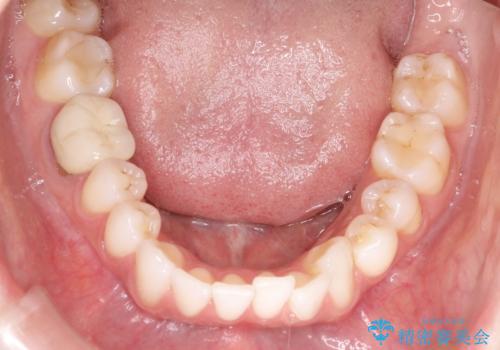

インビザラインによる非抜歯での八重歯の矯正

- 左上の八重歯と、上の歯のがたつきを主訴に来院されました。

上の奥歯を後方に移動させてスペースを作るのと、歯と歯の間をわずかに削り歯を並べる計画としました。

非常に強力的な患者様であったので、上下の正中も合わせ、ガタガタも改善することができました。